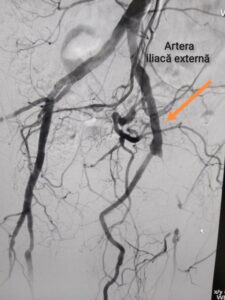

Medicii au luptat de două ori pentru viața acestui bolnav. Bărbatul inițial a fost operat peste hotarele țării, fiind diagnosticat cu o patologie arterială periferică. Acolo, lui i-a fost instalat un bypass femuro-popliteu cu proteză sintetică. Revenind acasă, rănile postoperatorii s-au infectat și s-a dezvoltat o patologie asociată protezei sintetice, infecție paraprotetică. Bolnavul a fost reoperat de această dată la IMSP SCR ”Timofei Moșneaga” , iar medicii au utilizat în loc de proteză, vena proprie a bolnavului, de la piciorul contralateral. După recoltarea probelor a lichidului din plăgile postoperatorii şi de pe suprafața protezei, s-a identificat agentul patogen cauzal ca fiind Staphylococcus aureus, meticilino-rezistent, cu care este foarte dificil de luptat. Această infecţie reprezintă un risc major pentru siguranța și viața bolnavului. La două luni după prima intervenție pacientul la domiciliu suferă o hemoragie erozivă din regiunea infrainghinală. Pacientul se reinternează în mod urgent în secția Chirurgia Vasculară pentru tratament chirurgical repetat. Pentru a salva membrul inferior al pacientului și a minimaliza riscul de hemoragie repetată din plaga infectată infrainghinală a fost luată decizia de a efectua protezarea extraanatomică transobturatorie ilio-poplitee cu autovenă. În Republica Moldova până la acest moment nu s-au efectuat astfel de operații, deși au existat pacienți eligibili pentru asta. Aceștia însă au fost abordați diferit, ținând cont de riscul major al operației.